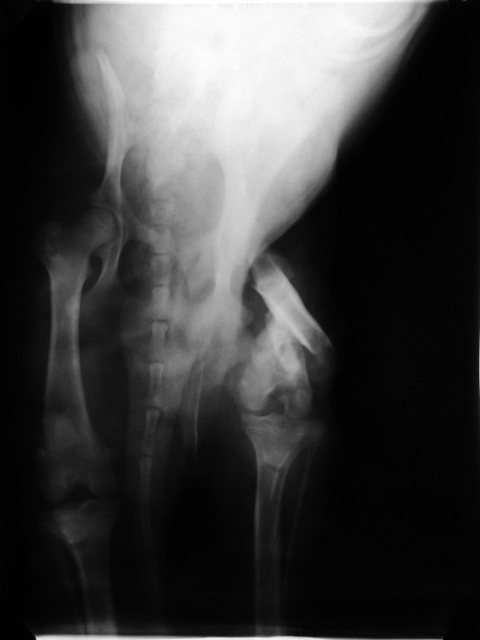

Die verletzte Hündin vom 12. August haben

wir in Urla röntgen lassen. Ihre Wirbelsäule ist

gebrochen und sie hat eine ausgeprägte Hüftdysplasie.

Wir haben sie daher leider gestern vom Tierarzt einschläfern

lassen müssen. Sowas nimmt einen jedesmal aufs Neue mit.

Das Röntgenbild zeigt einen Oberschenkelbruch mit einer

Verschiebung des Unterschenkels. Man kann es operativ richten,

aber die verheilte Haut ist noch zu frisch und zu stark durchblutet

für eine OP. Die Haut muss sich mindestens noch vier Wochen

regenerieren.